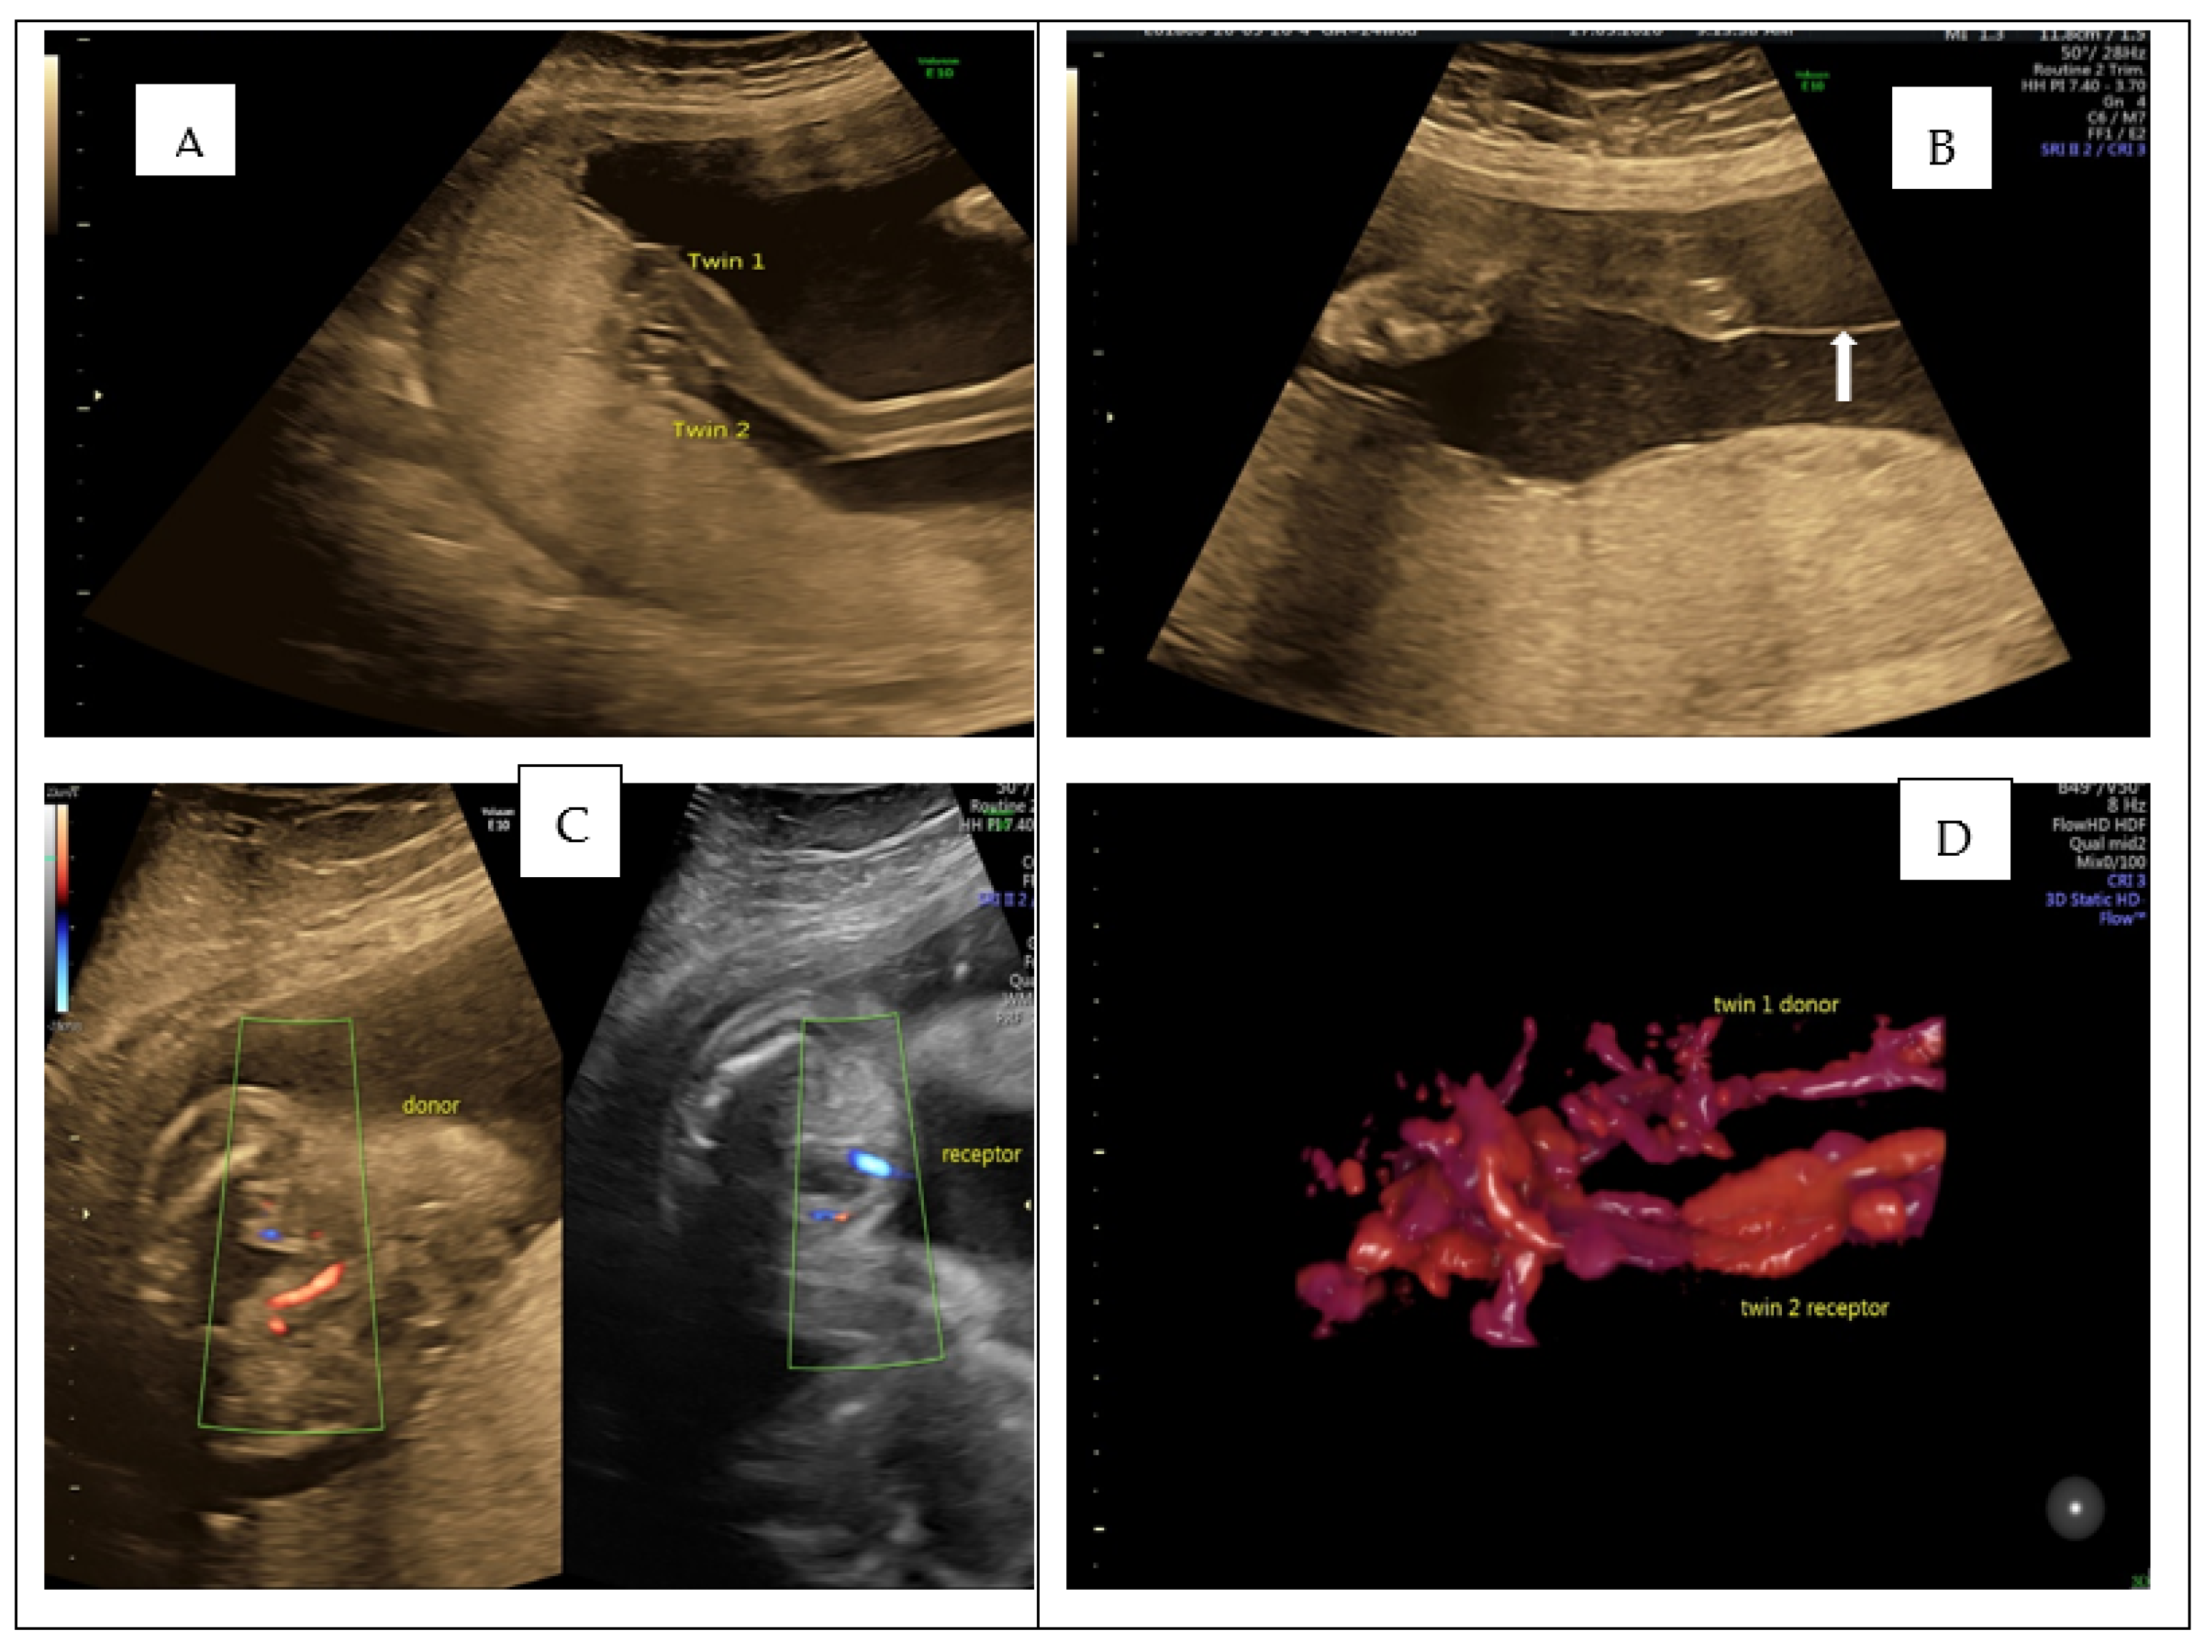

Ultrasound images in monochorionic diamniotic twin pregnancy with... Download Scientific Diagram Ultrasound Images Of Monochorionic Diamniotic Twins Twin pregnancies can be dichorionic or monochorionic (mc). Between 6 and 10 weeks’ gestation, a monochorionic twin pregnancy. In this review, we summarise the latest evidence relating to ultrasound surveillance of twin pregnancies including first trimester. (a) a dichorionic diamniotic twin pregnancy, in which the twins are separated by a thick layer of fused chorionic membranes;. In the first trimester,. Ultrasound Images Of Monochorionic Diamniotic Twins.